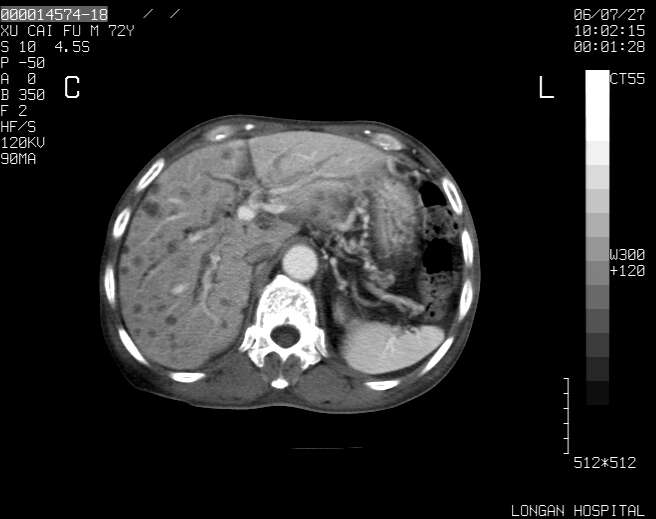

以下是引用winter在2006-7-30 20:14:00的发言:[br]1、考虑胆囊癌伴胆道侵犯并高位胆道梗阻、肝内多发转移、腹膜后淋巴结转移。[br]2、右肾轻度积水。[br]3、老人家72岁了胰腺头体尾部均较饱满,不过未见密度异常及其他异常征象。[br]4、腹水。

以下是引用jiajie在2006-7-31 7:10:00的发言:[br]考虑肝转移瘤,腹膜后淋巴结增大。[br]胃癌不能除外,建议胃镜检查。